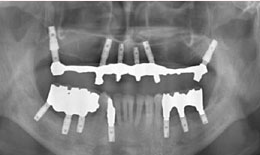

インプラント症例(25)50歳 男性

治療後

上顎

インプラントを6本埋め込んで、ボーンアンカードブリッジを装着した

下顎

インプラントを7本埋め込んで、セラミックスクラウンを被せた